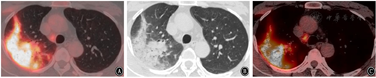

辅助检查。血常规:白细胞计数12.03×109/L,中性粒细胞比率89%。血生化:肝功能、肾功能、血脂、血糖未见异常,钠130.0 mmol/L,氯96.0 mmol/L。弥散性血管内凝血:纤维蛋白原9.45 g/L,D-二聚体1.34 mg/L,纤维蛋白原降解产物5.52 mg/L。C反应蛋白279.99 mg/L。ESR 70.0 mm/1 h。尿常规:尿蛋白(+),尿酮体(++)。腰椎穿刺送检脑脊液常规、生化、抗酸染色等结果未见异常。完善血培养、降钙素原、呼吸道九项病原体[包括嗜肺军团菌、肺炎支原体、Q热立克次体、肺炎衣原体、腺病毒、呼吸道合胞病毒、甲型流感病毒、乙型流感病毒和副流感病毒1、2和3型的主要病原体的IgM抗体]、血清1,3-β-D-葡聚糖检测和曲霉特异性抗原(半乳甘露聚糖)检测。行PET-CT提示如下。(1)右肺上叶大片状实性絮片影(图1),纵隔右下气管旁及右肺门多发稍大淋巴结,以上代谢增高,倾向考虑炎性,建议治疗随诊。(2)双眼未见异常密度及代谢,请结合临床;视野内骨及全身多处肌肉代谢弥散性增高,均考虑反应性改变;以上随诊。(3)脑部未见明显异常。(4)双肺尖散在局限性气肿,左肺尖小结节,未见异常代谢,多考虑良性增殖灶;余双肺散在索条。(5)脂肪肝:肝SⅡ及SⅤ段囊肿;肝SⅤ段钙化灶;双侧肾上腺局部结节状略增粗,未见异常代谢,多考虑良性,皮质增生或小腺瘤可能;升结肠弥散性代谢增高,考虑炎性或生理性摄取。(6)脊柱生理曲度变直。

2021年7月15日复查胸部CT显示肺部感染吸收好转(图2、图3),遂停用糖皮质激素,抗生素降阶梯为头孢曲松(2 g,静脉滴注,1次/d)。BALF mNGS回报后检索惠普尔养障体感染有关文献的治疗方法亦首选头孢曲松,故继续予以头孢曲松治疗,头孢曲松治疗1周后患者病情平稳出院。院外继续长期口服甲氧苄啶磺胺甲唑(0.96 g,2次/d)治疗,停用糖皮质激素,3个月随访时患者自诉视力下降、慢性腹泻、多关节痛均得到缓解,生活质量提高。2022年3月复查胸部CT右肺上叶肺炎吸收(图4)。目前患者仍在接受口服甲氧苄啶磺胺甲唑(0.96 g,2次/d)的治疗,继续随访。